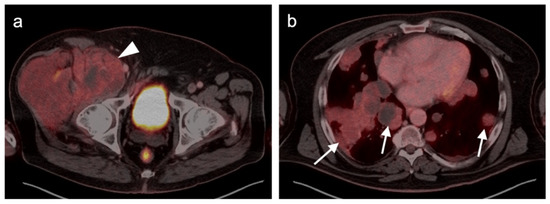

- Wong, V.K.; Lubner, M.G.; Menias, C.O.; Mellnick, V.M.; Kennedy, T.A.; Bhalla, S.; Pickhardt, P.J. Clinical and Imaging Features of Noncutaneous Melanoma. Am. J. Roentgenol. 2017, 208, 942–959. [Google Scholar] [CrossRef]

- Murphy, G.; Hussey, D.; Metser, U. Non-cutaneous melanoma: Is there a role for18F-FDG PET-CT? Br. J. Radiol. 2014, 87, 20140324. [Google Scholar] [CrossRef] [Green Version]